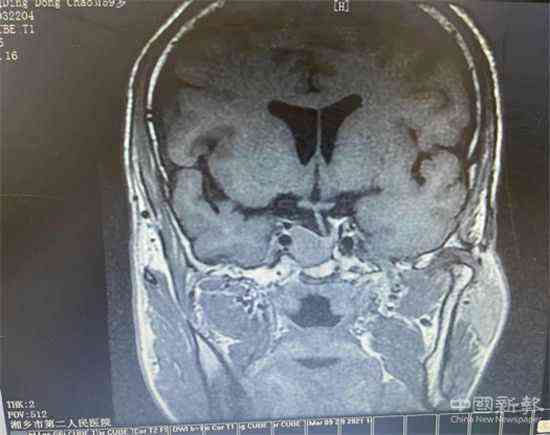

患者的垂體MRI彌散+動態(tài)增強(qiáng)影像資料

據(jù)了解,患者丁某有兩年的糖尿病病史,于2021年3月1日慕名來該院代謝內(nèi)分泌科住院治療。住院期間,丁某在血糖水平高的同時(shí),還伴有甲狀腺功能亢進(jìn)。但其檢測結(jié)果卻不符合常見的原發(fā)性甲狀腺功能亢進(jìn)表現(xiàn),呈TSH不適當(dāng)分泌,引起了張?jiān)屏种魅蔚母叨戎匾?。他認(rèn)為很有可能是腦垂體方面的問題或者甲狀腺激素不敏感綜合征。因此,建議患者進(jìn)一步做垂體的核磁共振彌散+動態(tài)增強(qiáng)、垂體功能檢測等針對性檢查,以確定病情。但患者因檢查費(fèi)用等方面的顧慮,不同意進(jìn)行針對性檢查。本著對病人高度負(fù)責(zé)的態(tài)度,張主任多次與患者耐心溝通,并積極向院方申請經(jīng)費(fèi)支持,全面打消患者各方面顧慮。在醫(yī)院和醫(yī)療團(tuán)隊(duì)的努力下,丁某接受了相關(guān)檢查。結(jié)果顯示:在患者蝶鞍處發(fā)現(xiàn)一較大的垂體腫瘤。結(jié)合臨床及其他輔助檢查,支持垂體TSH瘤這一診斷。